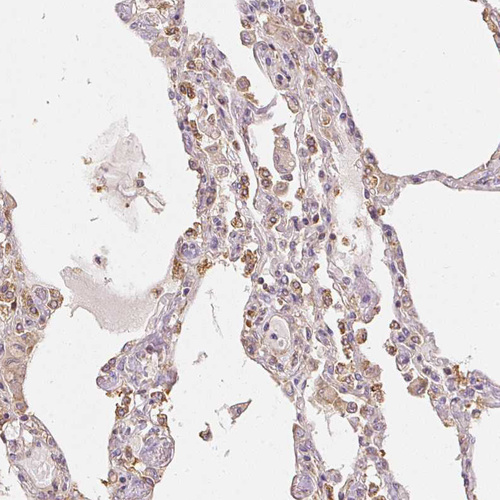

Immunohistochemical staining of human placenta shows strong cytoplasmic positivity in trophoblastic cells.